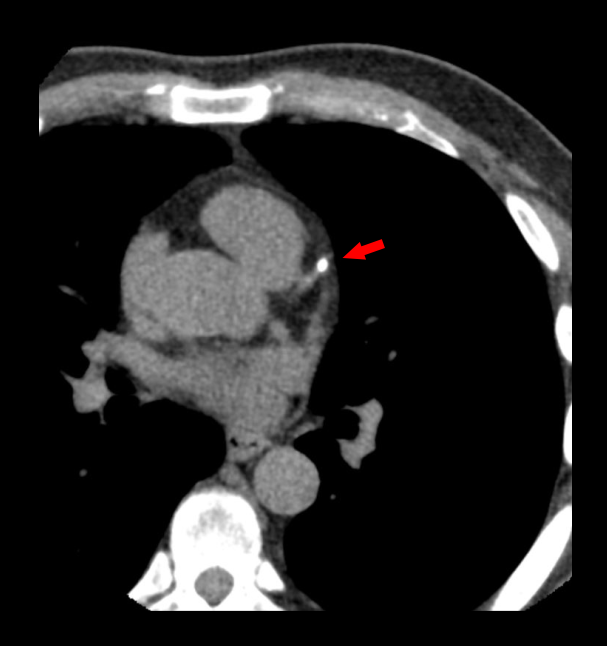

CT calcium score, which is a non-contrast study, is helpful to quantify coronary artery calcium deposits. It’s used for the risk stratification and therapeutic decision making in patients who are in risk of atherosclerotic cardio vascular risk. Moreover, in Transcatheter Aortic Valve Replacement (TAVR), calcium scoring is used to analyze the score of the aortic valve.

- Axial images in cardiac window (WW: 1000, WL: 400) with 3mm slice thickness.